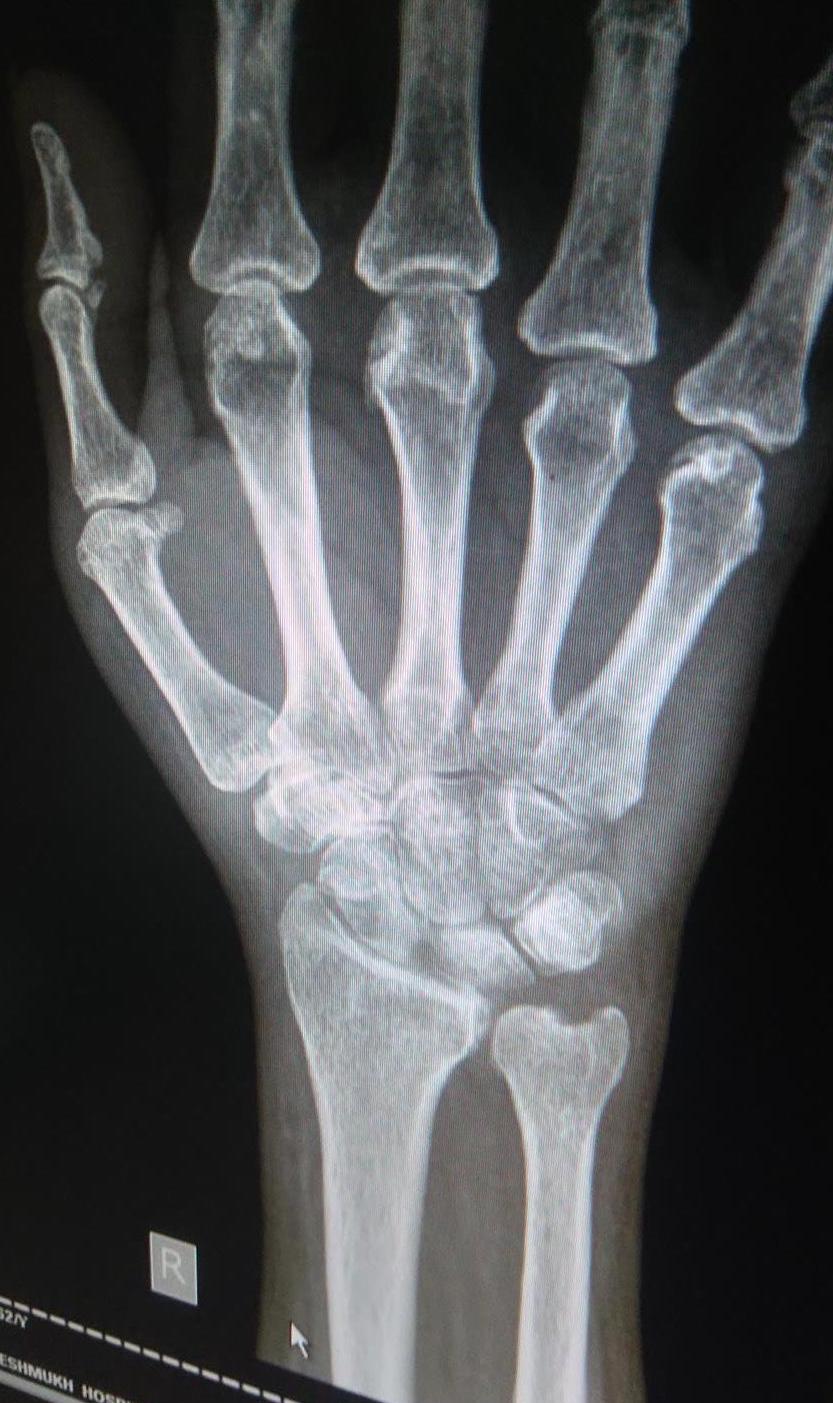

hand arthritis on xrays Raleigh Hand to Shoulder Center How To Detect Arthritis In Wrist Having painful arthritis in your wrist can make it hard to do many everyday activities. The physical exam will look for areas of pain, swelling and decreased motion. You may need to try several different. How arthritis in the wrist is diagnosed. The base of your thumb, your knuckles, second joint and top joint of your fingers are common sites. How To Detect Arthritis In Wrist.

WRIST OSTEOARTHRITIS, XRAY Stock Photo Alamy How To Detect Arthritis In Wrist The physical exam will look for areas of pain, swelling and decreased motion. How arthritis in the wrist is diagnosed. You may need to try several different. First, your doctor will ask about your symptoms and medical history and perform a physical exam. The base of your thumb, your knuckles, second joint and top joint of your fingers are common. How To Detect Arthritis In Wrist.